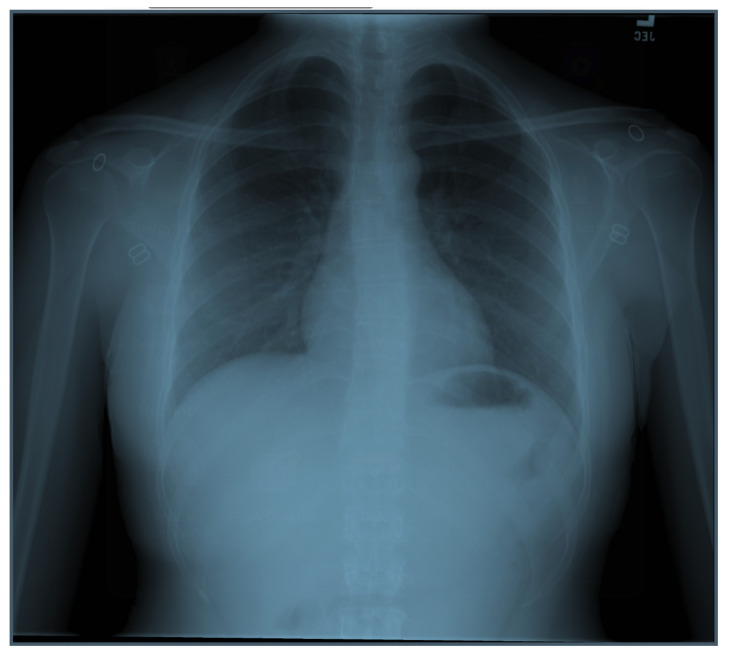

| #6 | Chest X-ray |

| Respiratory | Tachypneic. Breath sounds clear and equal bilaterally without any wheezing, crackles, or ronchi. |